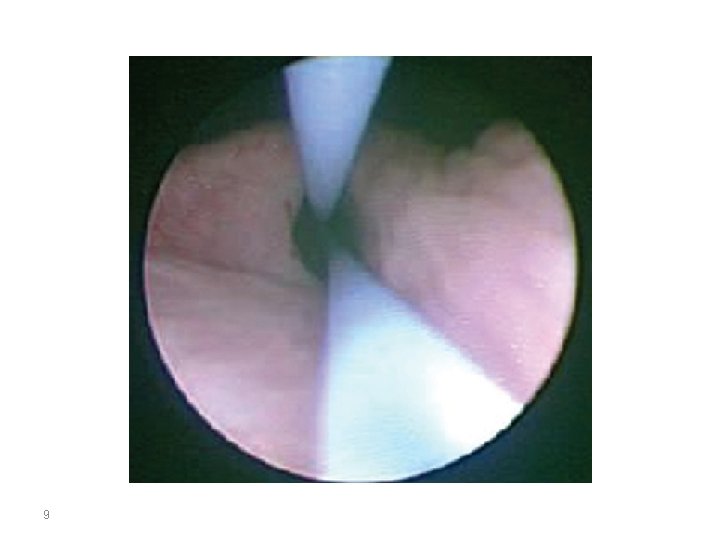

8 Ancillary Equipment Wires. Guidewires used during retrograde instrumentation serve to provide access to a particular area of the urinary tract and serve as a guide to pass catheters, stents, and sheaths. • • Guidewire properties vary with respect to length, diameter, composition, tip design, surface coating, and shaft rigidity. Guidewire diameters and lengths range from 0. 018 to 0. 038 inch and 145 to 280 cm, respectively. • • The ideal guidewire should have a flexible lubricous tip allowing for easy atraumatic passage through a tortuous, obstructed ureter while providing sufficient rigidity of the shaft for the passage of catheters and instruments. • • •

9

Care should be taken to use only as much irrigation needed to provide a clear visual field. Utilizing the minimum amount of irrigation necessary to provide a clear view during ureteroscopy minimizes stone migration, bleeding from hydrodistention, and pyelolymphatic or pyelovenous backflow. l The holmium: YAG laser is the gold standard for ureteroscopic intracorporeal lithotripsy. 10 • •